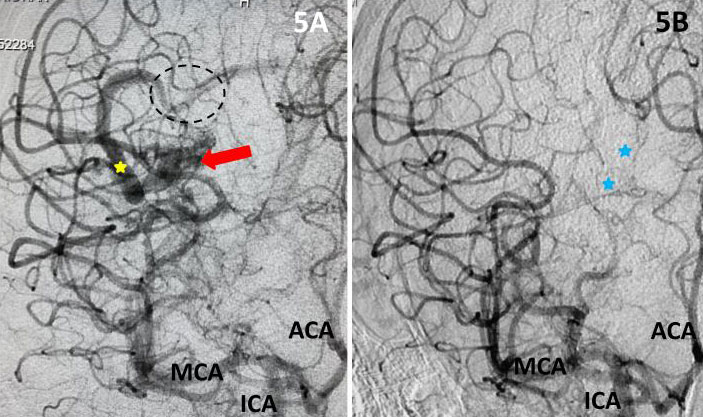

The student underwent NBCA-embolization of the AVM via the dominant feeding posterior cerebral artery with care to avoid embolizing the calcarine branches and avoid NBCA penetration into the single draining vein (Fig 4 and 5). Following the intervention, a tiny feeder from the middle cerebral artery remained (Fig 4).

Fig 4. Post-embolization lateral view (4A) and AP view (4B), late-arterial phase of a right internal carotid artery (ICA) injection. With near total obliteration of the AVM, a small MCA component (red arrow) can be seen working its way to the residual AVM (embolization material; yellow arrow). Residual veins (blue arrows) and spared calcarine branches of the posterior cerebral artery (CBr).

Fig 5. Comparison, pre (5A) and post-embolization (5B) AP view, late-arterial phase of a right internal carotid artery (ICA) injection. On the right, near total obliteration of the AVM (red arrow). Draining vein (yellow star), residual veins (blue stars).